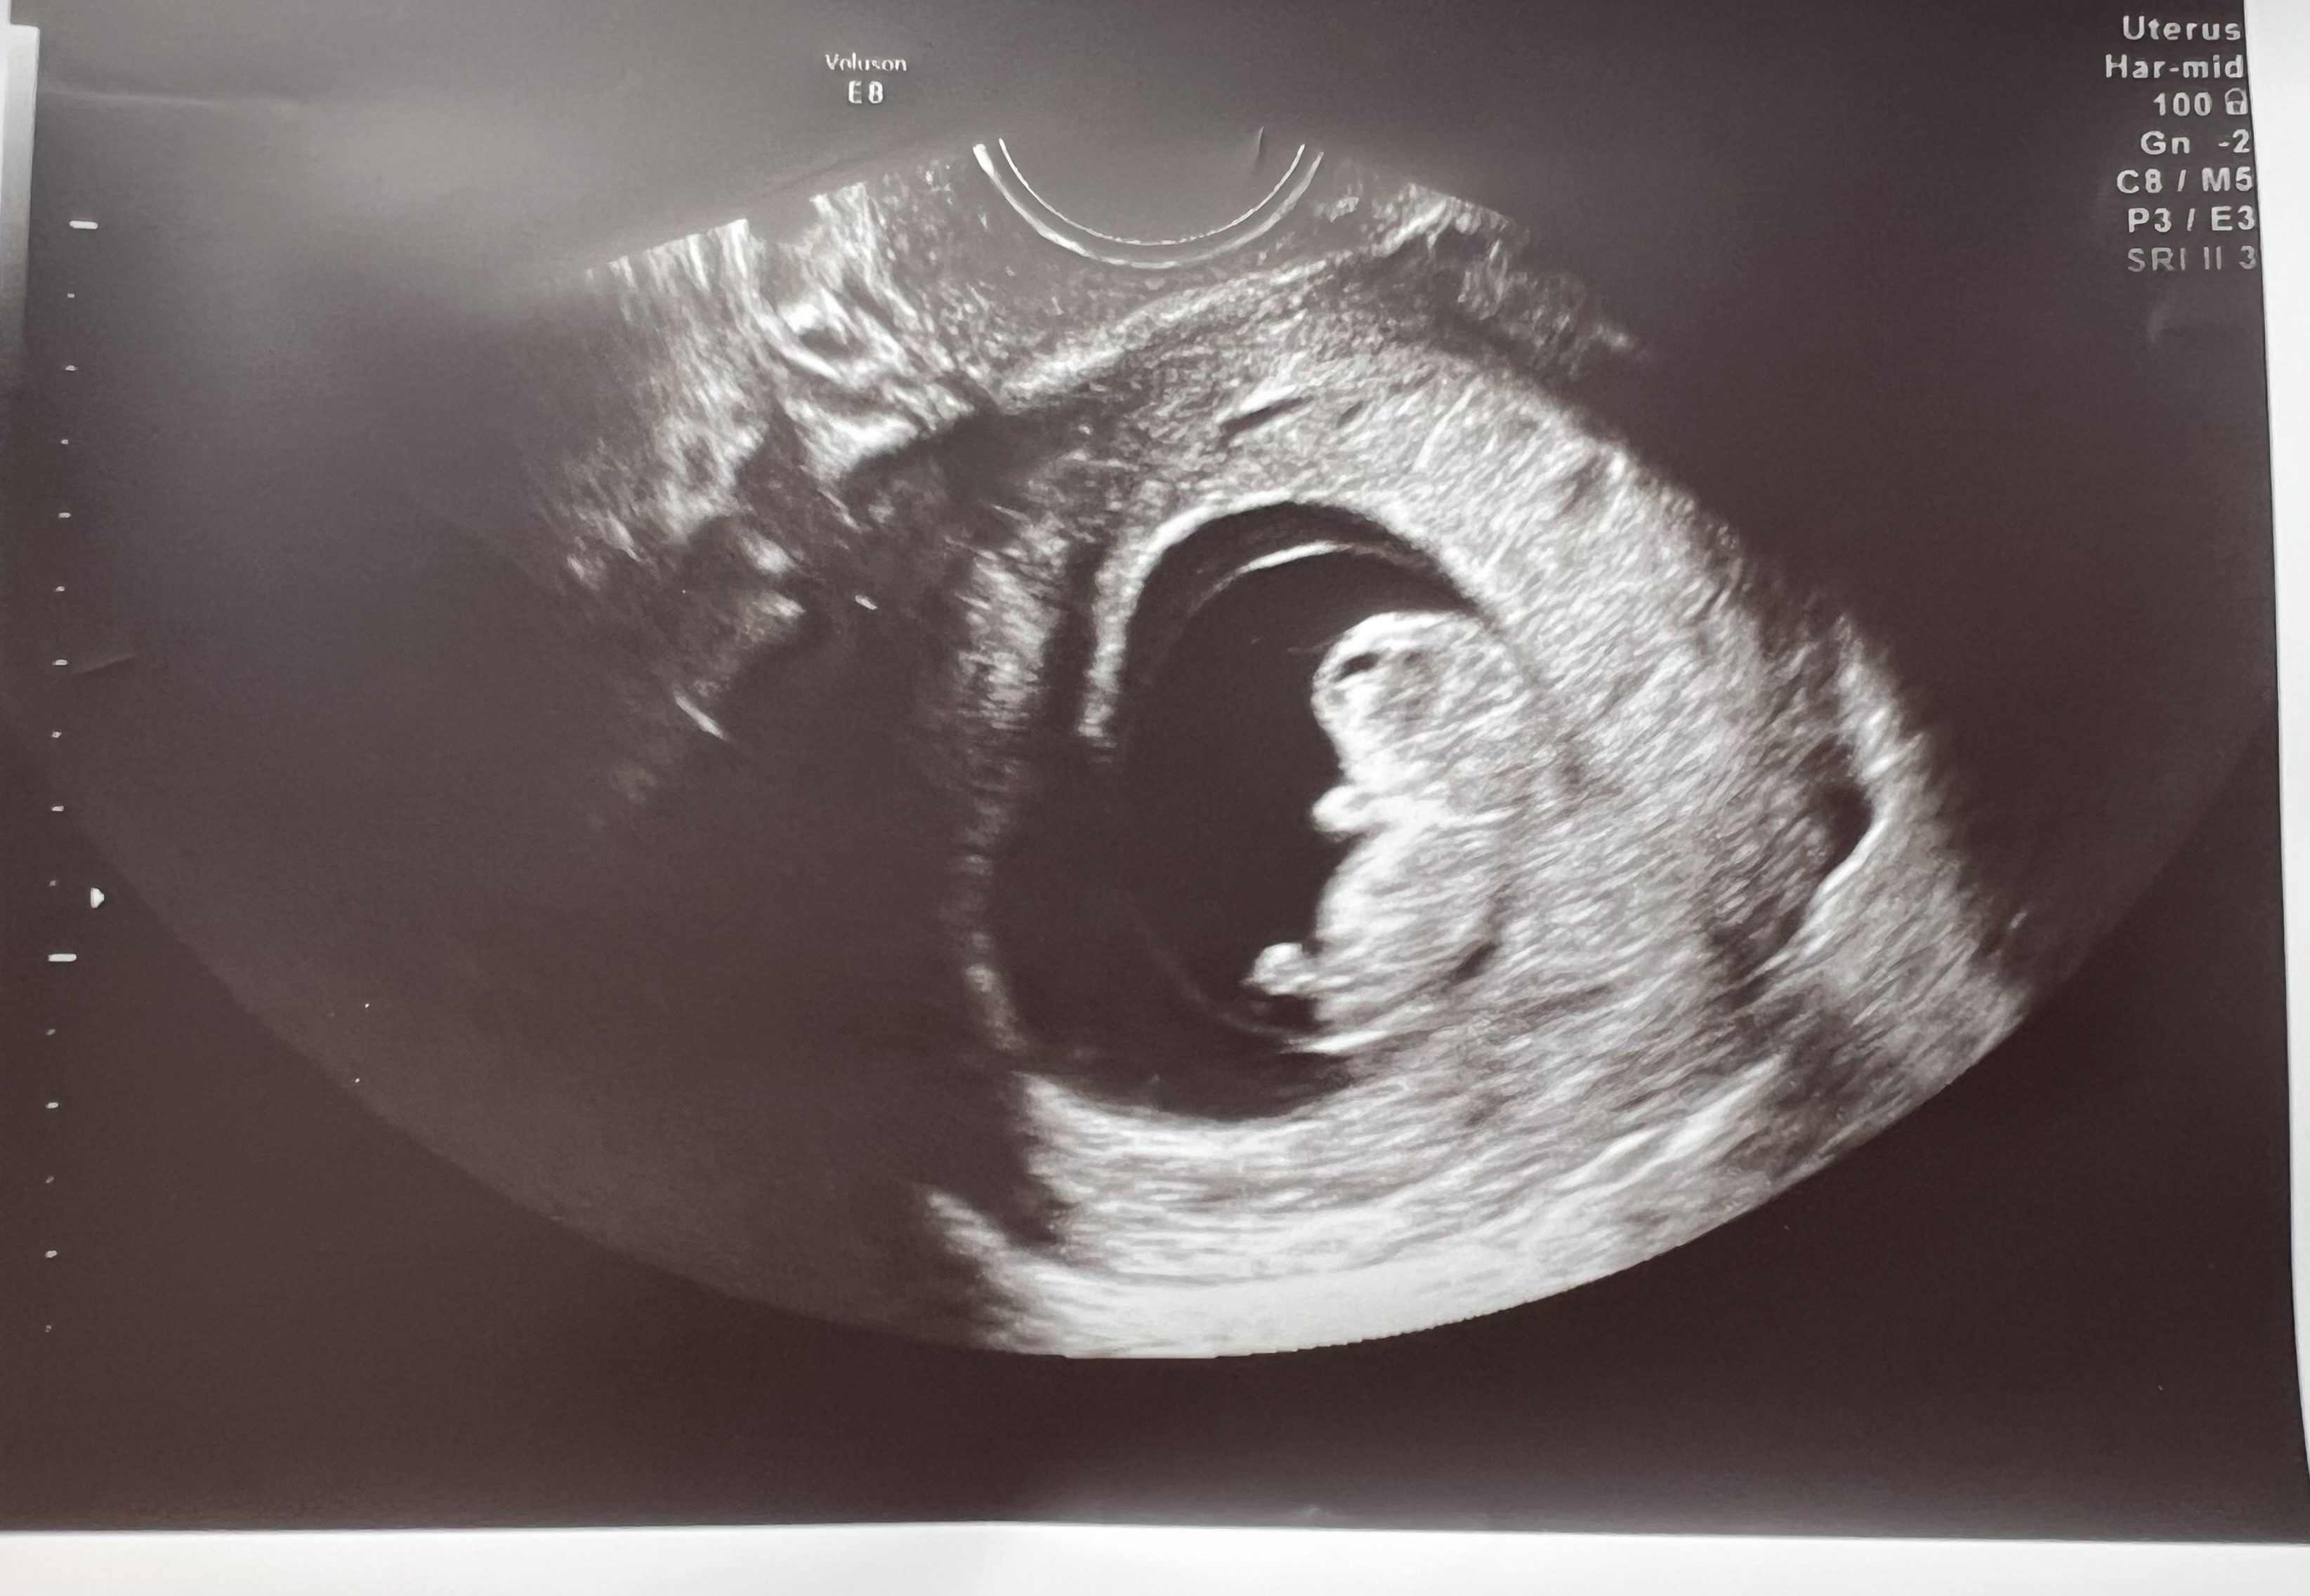

Z samego rana pojechaliśmy na SOR, ponieważ zobaczyłam dużo świeżej, żywej krwi. Oczywiście od razu spanikowałam, że to na pewno koniec. Na szczęście maluch ma się dobrze, ma już 3 cm! Dziś 9+4, a wymiarami odpowiada 9+6. Kamień z serca

naprawdę jechałam tam przygotowana na najgorsze

Nie mogę przestać wpatrywać się w to zdjęcie, widać już nóżki i rączki